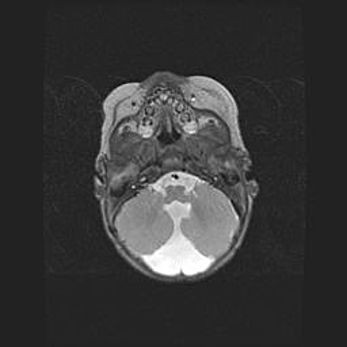

Подострая гематома правой гемисферы мозжечка.

Наружная гидроцефалия.

Возраст: 15 дней

Вес: 3100 г

Пол: женский

Окружность головы: 37 см

Срок гестации: 35-36 недель

При открытой наружной форме гидроцефалии у новорожденных расширяются и переполняются субарахноидные пространства.

Кровоизлияния в мозжечок имеют две клинико-анатомические формы: полушарные гематомы и кровоизлияния в червь.

К появлению этой патологии может привести: повреждения головного мозга, возникающие в результате асфиксии и гипоксии плода при беременности, или травмы во время родов. Редко гематома мозжечка может быть результатом первичной коагулопатии и сосудистой мальформации, диссеминированном внутрисосудистом свертывании, изоиммунной тромбоцитопении.